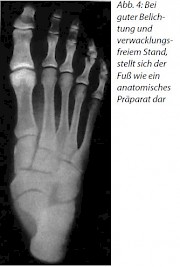

Die Aufnahmetechnik des Fußes im Stehen mit Doppelbelichtung erlaubt die Darstellung des Fußes wie ein anatomisches Präparat ohne Unterschenkel.

Die Aufnahme gelingt nur, wenn der Fuß ruhig gehalten wird und wenn genau auf die Längsachse des Fußes zentriert wird, um die Doppelkonturen zu vermeiden!